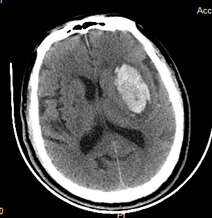

小骨窗开颅脑内血肿清除术

出院:GCS评分15分,双侧瞳孔圆形等大,直径2.5mm,对光反射灵敏。右侧上肢肌力Ⅰ级,右下肢肌力Ⅱ级,左侧肌力正常,肌张力未见异常,双侧巴氏征阴性。

术前                           术后